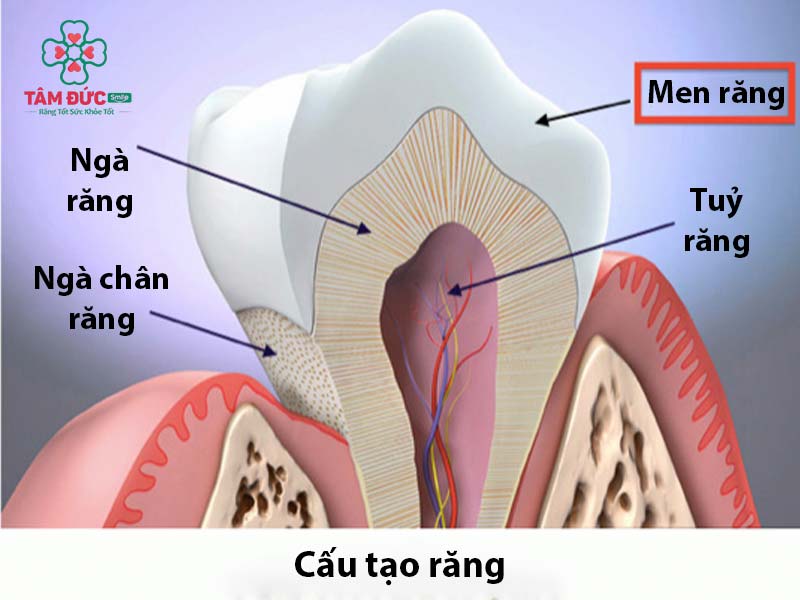

Men răng là vật liệu cứng nhất trên cơ thể của chúng ta với hàm lượng cực cao canxi phosphat (lên tới 95%). Được hình thành thông qua quá trình khoáng hóa protein tạo thành một lớp có màu – đây là thành phần tạo nên màu sắc cho răng.

Men răng là lớp mà Quý khách có thể nhìn thấy được bằng mắt thường. Lớp này màu trắng, rất bền và khó bị vỡ, bao bọc xung quanh thân răng.

- Giúp bảo vệ ngà răng, tủy răng: Là bộ phận rất quan trọng của răng có tác dụng định hình và làm cho răng vững chắc. Tủy răng có vai trò tái tạo lại ngà răng và tiếp nhận, thông báo cho Quý khách biết những tín hiệu có hại.

- Là một lớp ngăn cách nhiệt: Giúp ngăn cản tủy răng có thể cảm nhận được nhiệt độ giúp giảm bớt tình trạng ê buốt răng.

- Hỗ trợ chức năng nhai: Nhờ vào lớp canxi rắn chắc, răng có thể nghiền những thức ăn thông thường một cách dễ dàng.

Men răng là lớp ngoài cùng của răng